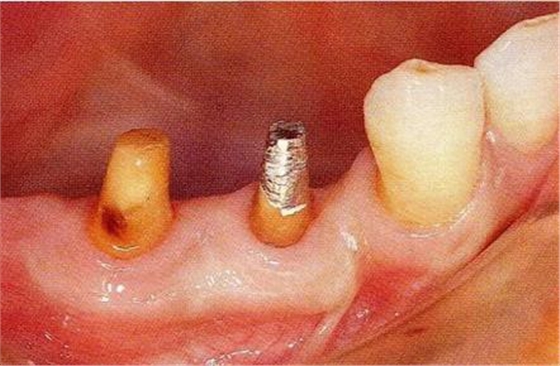

圖17-3▲拔牙的同時做骨外科處理,讓殘留的骨可以盡量平坦化。為了獲得頰側(cè)的附著齦,采用了游離齦瓣的處理。